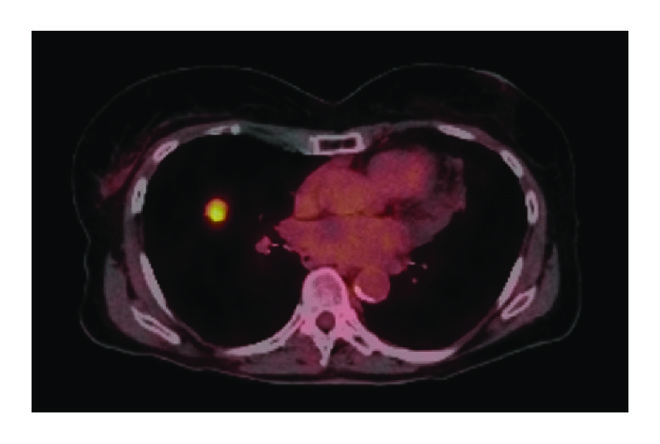

(a)

(b)

(c)

For the 108 patients included in this study, we found 195 instances of disease progression on ET that prompted a change in therapy. Progression was characterized as follows: diffuse progression, progression in greater than 3 sites; oligoprogression, progression in fewer than 3 sites with prior diffuse metastases (>6 sites of disease); and oligometastatic disease with progression, progression in 3 or fewer sites with prior limited metastases (<6 sites of disease). Examination of the patterns of failure revealed diffuse progression in 150 courses (77%), oligoprogression in 28 courses (14%), and oligometastases with progression in 18 courses (9%). On a per patient basis, most patients (69%) displayed only diffuse disease progression, with a smaller percentage of patients displaying oligoprogression (21%) or oligometastases with progression (10%) at least once in their disease course. Though these patients with oligoprogression or oligometastases with progression were similar in age and prior treatment to those patients who progressed diffusely, the patients who progressed diffusely were more likely to be Her2− (84% versus 74%, ), have more than 6 sites of disease at metastatic diagnosis (80% versus 56%, ), and have boney metastases (72% versus 47%, ) (Table 3). Additionally, though the median time to progression with each course of ET appeared similar between the two groups (Table 2), the overall survival of the patients that displayed diffuse progression was significantly shorter than the patients with oligoprogression or oligometastases with progression (median survival 3.1 years versus 6.5 years, ) (Figure 1(b)).

Of the 23 patients with oligoprogressive disease, 11 patients had only one site of progressive disease, 10 patients had two sites of progressive disease, and 2 patients had three sites of progressive disease. The most common sites of oligoprogression were bone (), liver (), locoregional (), and lung () (Figure 2). In addition, mixed locoregional and boney metastases were noted in two patients and one patient developed brain metastasis. Unfortunately, given the limited number patients in this study, no treatment or demographic factors were identified that were specifically associated with oligoprogression.

As noted above, ablation of sites of oligoprogression has demonstrated clinical benefit in other malignancies. Therefore, while characterization of the pattern of progression for patients with metastatic estrogen receptor positive breast cancer was the primary aim of this study, we also sought to identify if any of the patients with apparent oligoprogressive disease would have been amenable to ablative therapy. Stereotactic body radiation therapy (SBRT) was selected as the modality to be assessed as it has demonstrated efficacy in other malignancies, is noninvasive, and has documented low rates of significant morbidity. Of the patients with oligoprogressive disease, 14 (61%) had disease deemed amenable to ablative therapy (Supplemental Table in Supplementary Material available online at https://doi.org/10.1155/2017/1367159). The patients with disease amenable to ablation included 7 patients with spinal metastasis, 4 patients with liver metastasis, 2 patients with lung metastasis, and 1 patient with brain metastasis. Seven patients had one lesion, 5 patients had 2 lesions, and 2 patients had 3 lesions.